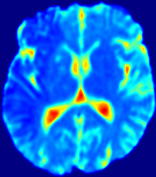

Figure 4: PIANO feature maps for another patient in the ISLES 2017 training set, where the lesion is located in the right hemisphere. Top row: segmented stroke lesion region (white) on different slices. The corresponding slices for the PIANO feature maps are shown in the following rows.

For a better insight into an estimated velocity field 𝐕𝐕{\bf{V}} and diffusion field 𝐃𝐃{\bf{D}}, we compute the following maps: (1) 𝐕rgbsubscript𝐕𝑟𝑔𝑏{\bf{V}}_{rgb}: Color-coded orientation map of 𝐕=(Vx,Vy,Vz)T𝐕superscriptsuperscript𝑉𝑥superscript𝑉𝑦superscript𝑉𝑧𝑇{\bf{V}}=(V^{x},V^{y},V^{z})^{T}, obtained by normalizing 𝐕𝐕{\bf{V}} to unit length and mapping its 3 components to red, green, blue respectively; (2) 𝐕2subscriptnorm𝐕2\|{\bf{V}}\|_{2}: 222 norm of 𝐕𝐕{\bf{V}}; (3) D𝐷D: scalar field in Eq. 5.

Fig. 3 and Fig. 4 show the PIANO feature maps estimated from two ISLES 2017 patients: all are highly consistent with the lesion in both cases. Details of the blood flow trajectories are revealed in 𝐕rgbsubscript𝐕𝑟𝑔𝑏{\bf{V}}_{rgb} by the ridged patterns and the sharp changes of colors in the unaffected (right) hemisphere, while the flat patterns appearing within the lesion provide little directional information about the velocity and indicate low velocity magnitudes. Velocity magnitudes are more directly visualized via 𝐕2subscriptnorm𝐕2\|{\bf{V}}\|_{2}, from which one can easily locate the lesion where 𝐕2subscriptnorm𝐕2\|{\bf{V}}\|_{2} is low. D𝐷D also indicates lower diffusion values in the lesion, though with less contrast potentially due to the fact that it captures the accumulated effect of CA diffusion at the voxel-level.